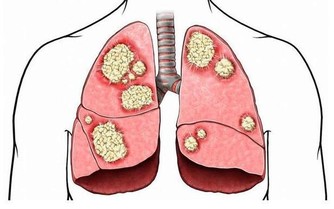

腎小球腎炎、糖尿病腎病、高血壓腎病、痛風腎、多囊腎等都被統稱為“慢性腎病”。當腎臟受損時,患者體內的毒素難以被過濾,逐漸會引起上述症狀。而這類疾病通常無法根治,唯有找到致病原因、確定疾病類型,才能通過相應的治療控制病情,緩解不適感。常見的檢查方法包括血液檢查、放射性核素腎掃描、活體組織檢查等。

慢性腎病患者一般需要接受哪些治療呢?這就要根據患者的病情以及病因來確定。例如患者體內血紅蛋白水平偏低、出現貧血時,需要輸血、服用硫酸亞鐵藥片或者鐵元素補充劑。還有部分腎病患者無法正常排解體內的磷酸鹽,這時他們必須要控制磷酸鹽的攝入,盡量避免食用乳製品、紅肉、雞蛋以及魚類。皮膚瘙癢的患者,可以服用抗組胺劑(如氯酚胺)緩解不適。

如果患者進入了腎病五期,腎功能已經大幅衰竭時,只採取藥物治療和飲食控制遠遠不夠。因為這時的腎臟基本失去了過濾和排除毒素的功能,需要通過腎透析或腎臟移植才能維持正常運轉,但是這兩種方法很有可能會引起嚴重的並發症。